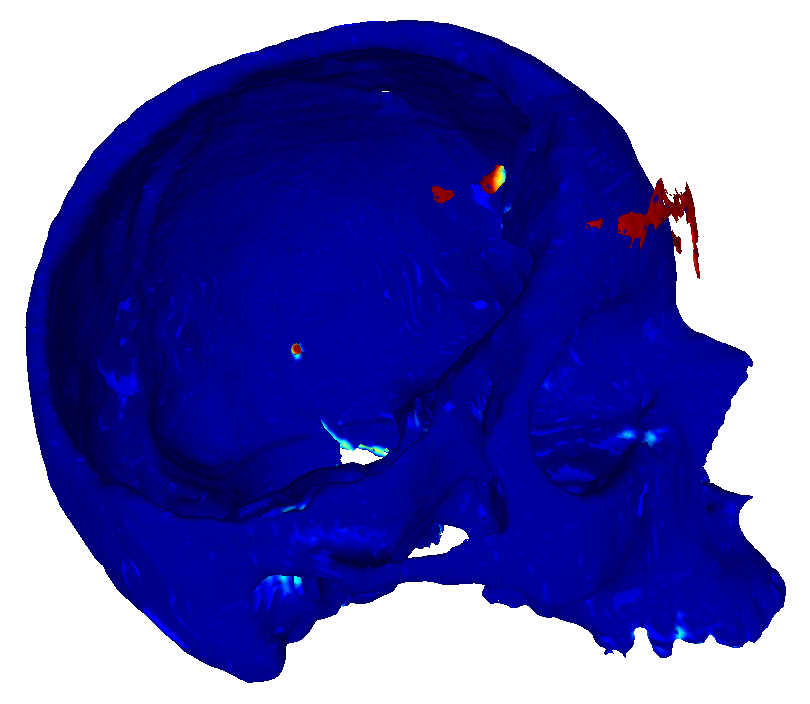

22 scans were randomly selected as test subjects for the experiment, leaving 177 skulls for model training. Using convolutional kernels of size 3 in all the CNN models results in the 3D model having the same number of trainable parameters as the sum of the three orthogonal 2D models. The comparison between the MV ensemble and the 3D approach can therefore be considered an ablation study to an extent. CutCNN models also have a similar number of parameters, the only difference being the final edge probability output layer. Quantitative comparison of results of each method are presented in Figure 4 and Table 1. Further qualitative results are shown in Figure 5 and 1.

CutCNN segmentation framework resulted in a performance gain in all cases in terms of every metric used in the experiment over standard CNN approaches. The output of CNN object probability map often contains errors near external objects or smaller tissue defects as these are scarce in the training data distribution. However, the graph-cut optimization guides the resulting binary segmentation towards a spatially consistent and compact shape, often eliminating these artifacts if a detected edge corresponds mostly to the correct object boundary. This effect is further illustrated in Fig. 1.